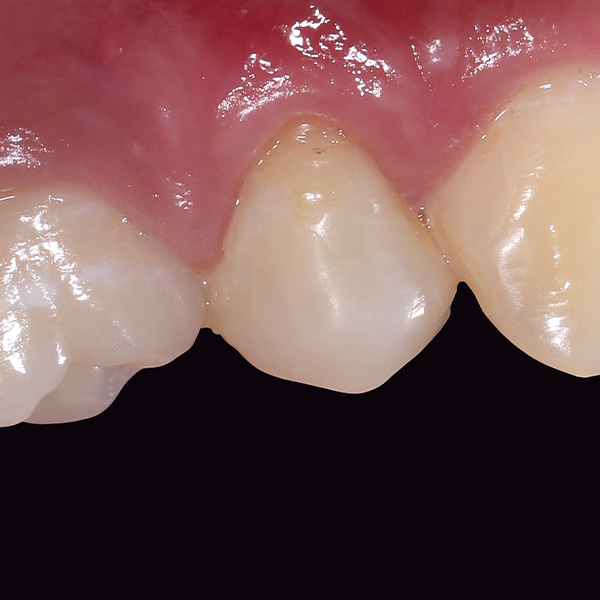

VITA ENAMIC multiColor Endokrone: Ausgangssituation vs. Finales Ergebnis

Ergebnis: VITA ENAMIC multiColor integrierte sich harmonisch in die natürliche Zahnsubstanz. Die insuffiziente Kompositfüllung an Zahn 14 (od) hatte zu Entzündungen im Zahnzwischenraum geführt.